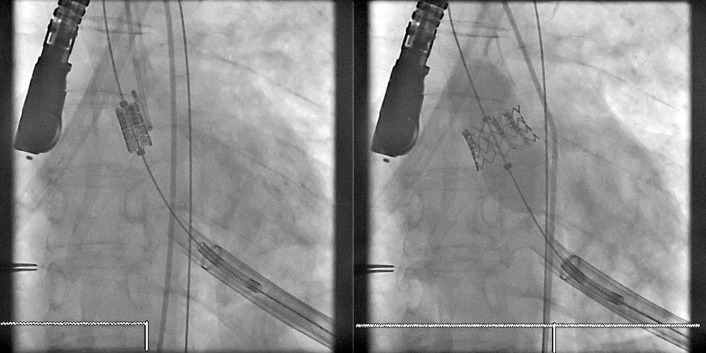

Transcatheter/percutaneously inserted heart valves are increasingly implanted. Most commonly, they are inserted into the pulmonic position or right heart conduits in the previously repaired congenital heart disease population ( Figs. 13-1 and 13-2 ) and into the aortic position ( Table 13-1 ; Graphics 13-1 and 13-2 ; Figs. 13-3 to 13-10 ), but they can also be placed into atrioventricular valve positions and into bioprostheses or conduits in any position.

Percutaneous valves are generally supported by radiographically obvious stents, the design of which allows for initial contraction of the prosthesis onto a catheter and release/self-expansion from the catheter.

Percutaneous/transcatheter heart valves are constructed of either bovine jugular venous valves that are suspended on wire mesh cages (Bonhoeffer design/Melody Transcatheter Pulmonary Valve–TPV, Medtronic), or consist of a valve created from bovine pericardial tissue that is suspended on wire mesh cages (Edwards Sapien and Medtronic CoreValve). Percutaneous aortic valve implantation is currently one of the most rapidly proliferating percutaneous interventions in the world ( Figs. 13-11 to 13-13 ).